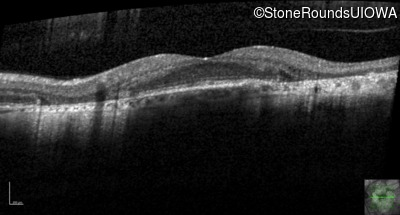

Age at visit: 51 years

This 51 year old woman first experienced some abnormality in her distance vision when she was 27 years old. She feels that her vision has been stable since that time.